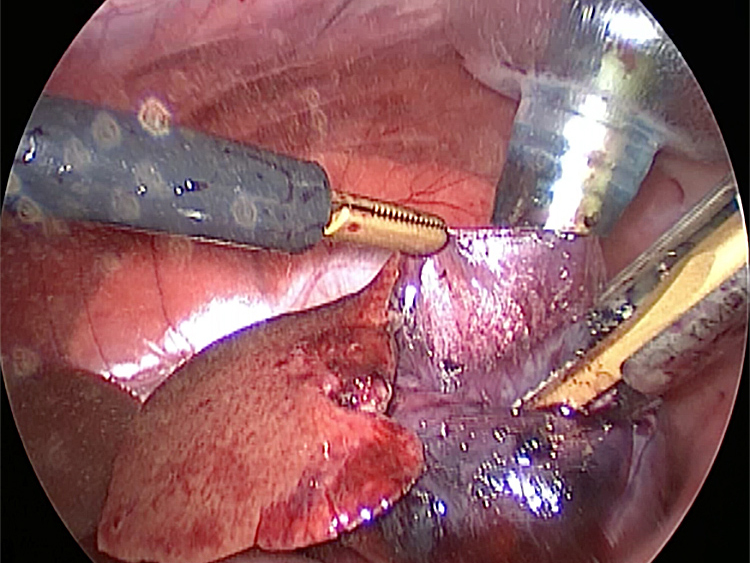

癒着(矢印)がひどく胆嚢を確認することができませんでした。 このように癒着しているときはギリギリで剥がすとひどく出血をおこすことがあるので無理にはがそうとしないで、脂肪の血管に注意しながら脂肪ごと剥がしていきます。

このときに胆嚢と一緒にクリップやガーゼも回収します。そしてお腹の中をきれいにしていきます。

最後にお腹の中をきれいに洗浄していきます。

胆嚢は分厚くなり周りには脂肪が張り付いていました。手術をして元気になりました。

回収袋にいれて体外に摘出していきます。

お腹の中を洗浄して終了となります。